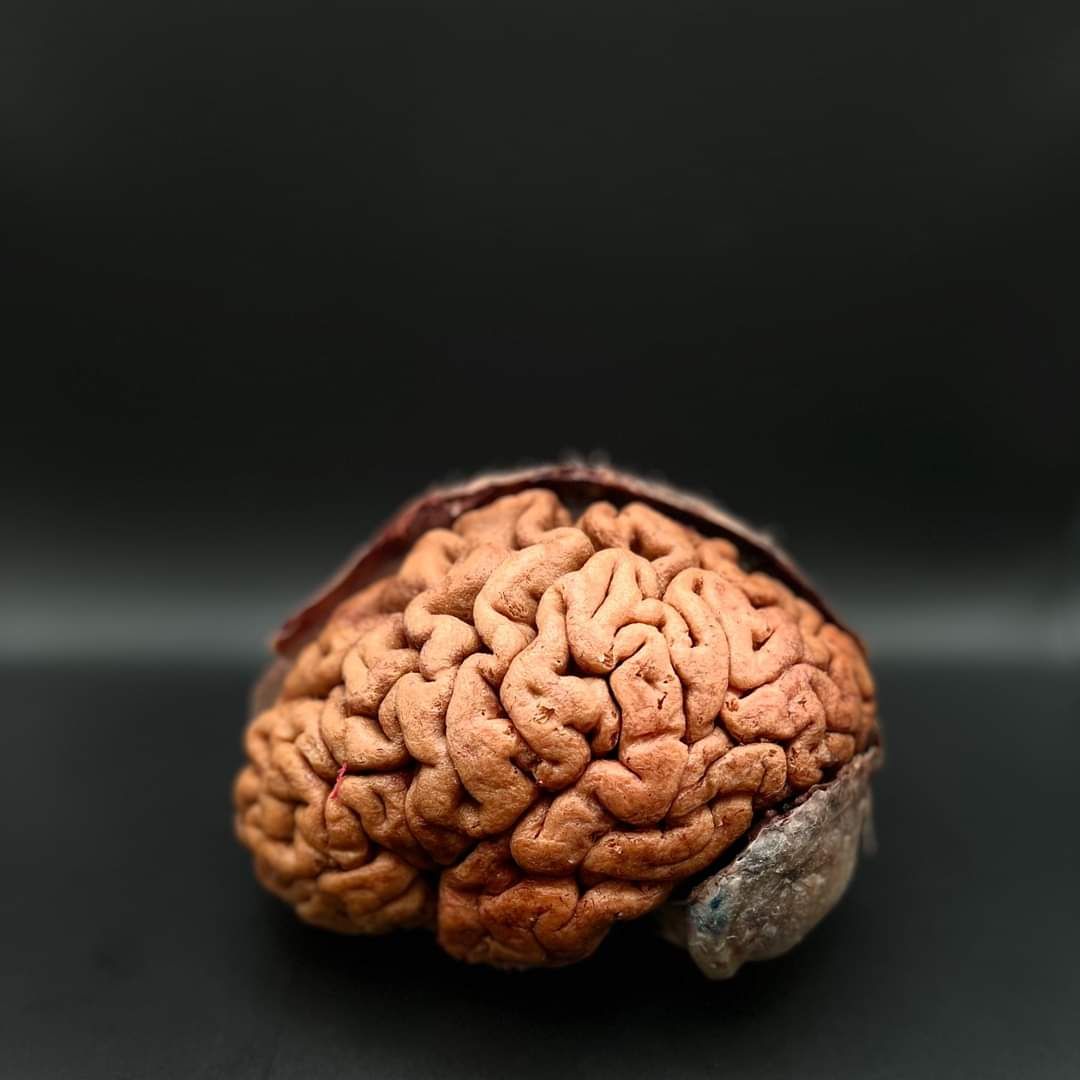

Resección de tumores cerebrales

Cirugía cerebral

El neurocirujano realiza diversos tipos de cirugía craneal, según la enfermedad del paciente. Entre las más comunes están la resección de tumores cerebrales, el clipaje de aneurismas para prevenir hemorragias, la cirugía de epilepsia, drenaje de hematomas, y la colocación de válvulas en casos de hidrocefalia. También se tratan malformaciones vasculares, neuralgias y algunos casos de traumatismo craneal. Cada procedimiento se adapta al caso, buscando siempre el mejor resultado con la menor invasión posible.